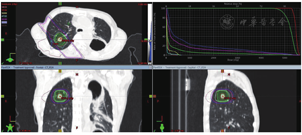

患者拒绝行CT引导下肺穿刺,未行化疗联合靶向治疗,于2016年6月行右肺转移灶精确放疗,仰卧位,负压袋固定体位,激光灯摆位,CT扫描,TPS优化放疗计划,IMRT技术,给予右肺转移灶精确放疗,5.0Gy/次,计划10次,总剂量50Gy。危及器官受量:脊髓最大受量4347cGy,心脏平均受量157cGy,右肺平均受量2622cGy,左肺平均受量474cGy,双肺平均受量289cGy,V20=5%(病例22图3)。放疗结束后胸部CT扫描示病变体积明显缩小,近期疗效PR优。放疗结束1个月,再次发现右肺新发转移,并再次给予大分割放疗(50Gy/10次,病例22图4),3个月后病情基本稳定,出现发热、咳嗽、胸闷、憋气,并逐渐加重,CT诊断为急性放射性肺炎(病例22图5),给予甲强龙,氧气吸入,抗感染,雾化等治疗好转后出院,失访。

3.经过选择的肺内单发转移或寡转移,SABR/SBRT不失为一种有效的治疗方法。治疗计划需评估好周围危及器官受照剂量和体积,具体可参考病例22图6。放射性肺炎是放疗后的严重不良反应,临床需特别注意预防和及时妥善处理。